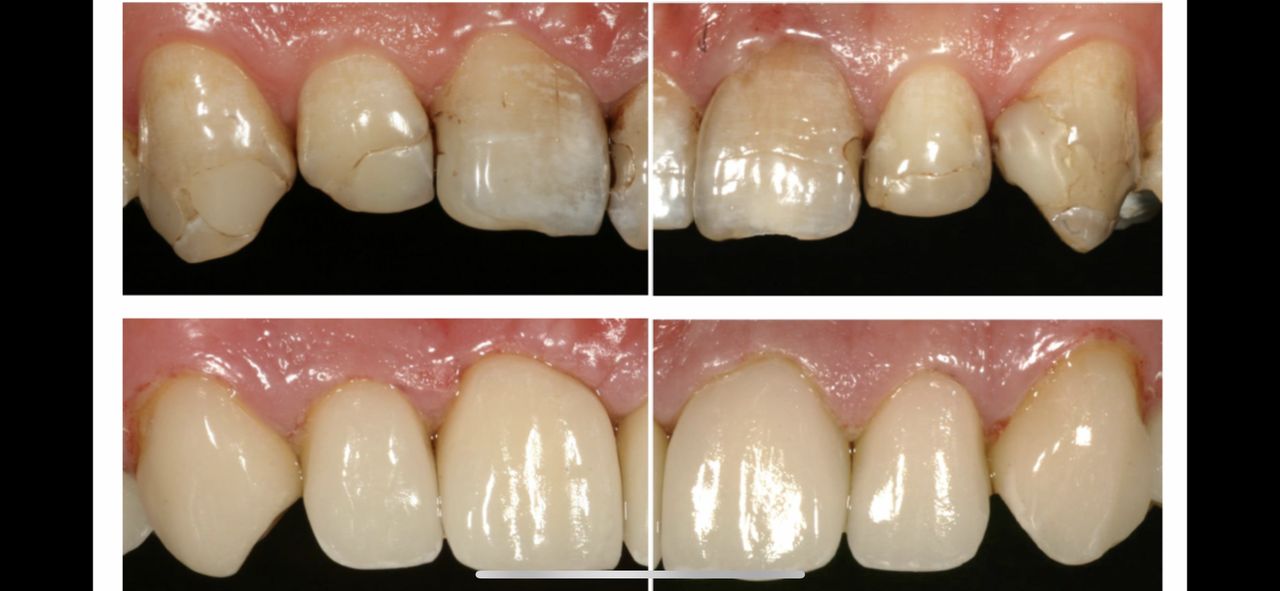

• Korony cyrkonowe

Od 1 600 zł

• Korony pełnoceramiczne

Od 1 200 zł

Z pełnym przekonaniem polecam leczenie protetyczne w tym gabinecie. Wykonane korony porcelanowo-cyrkonowe spełniły moje oczekiwania zarówno pod względem estetycznym, jak i funkcjonalnym. Efekt końcowy jest bardzo naturalny, korony są idealnie dopasowane i komfortowe w codziennym użytkowaniu. Cały proces leczenia przebiegał sprawnie, z dokładnym omówieniem planu oraz poszczególnych etapów. Lekarz wykazał się dużą wiedzą, precyzją i dbałością o detale, co w protetyce ma kluczowe znaczenie. Dodatkowo czułem się zaopiekowany i spokojny, co zdecydowanie podnosi komfort leczenia.

• Duo-Dent korony cyrkonowe  •